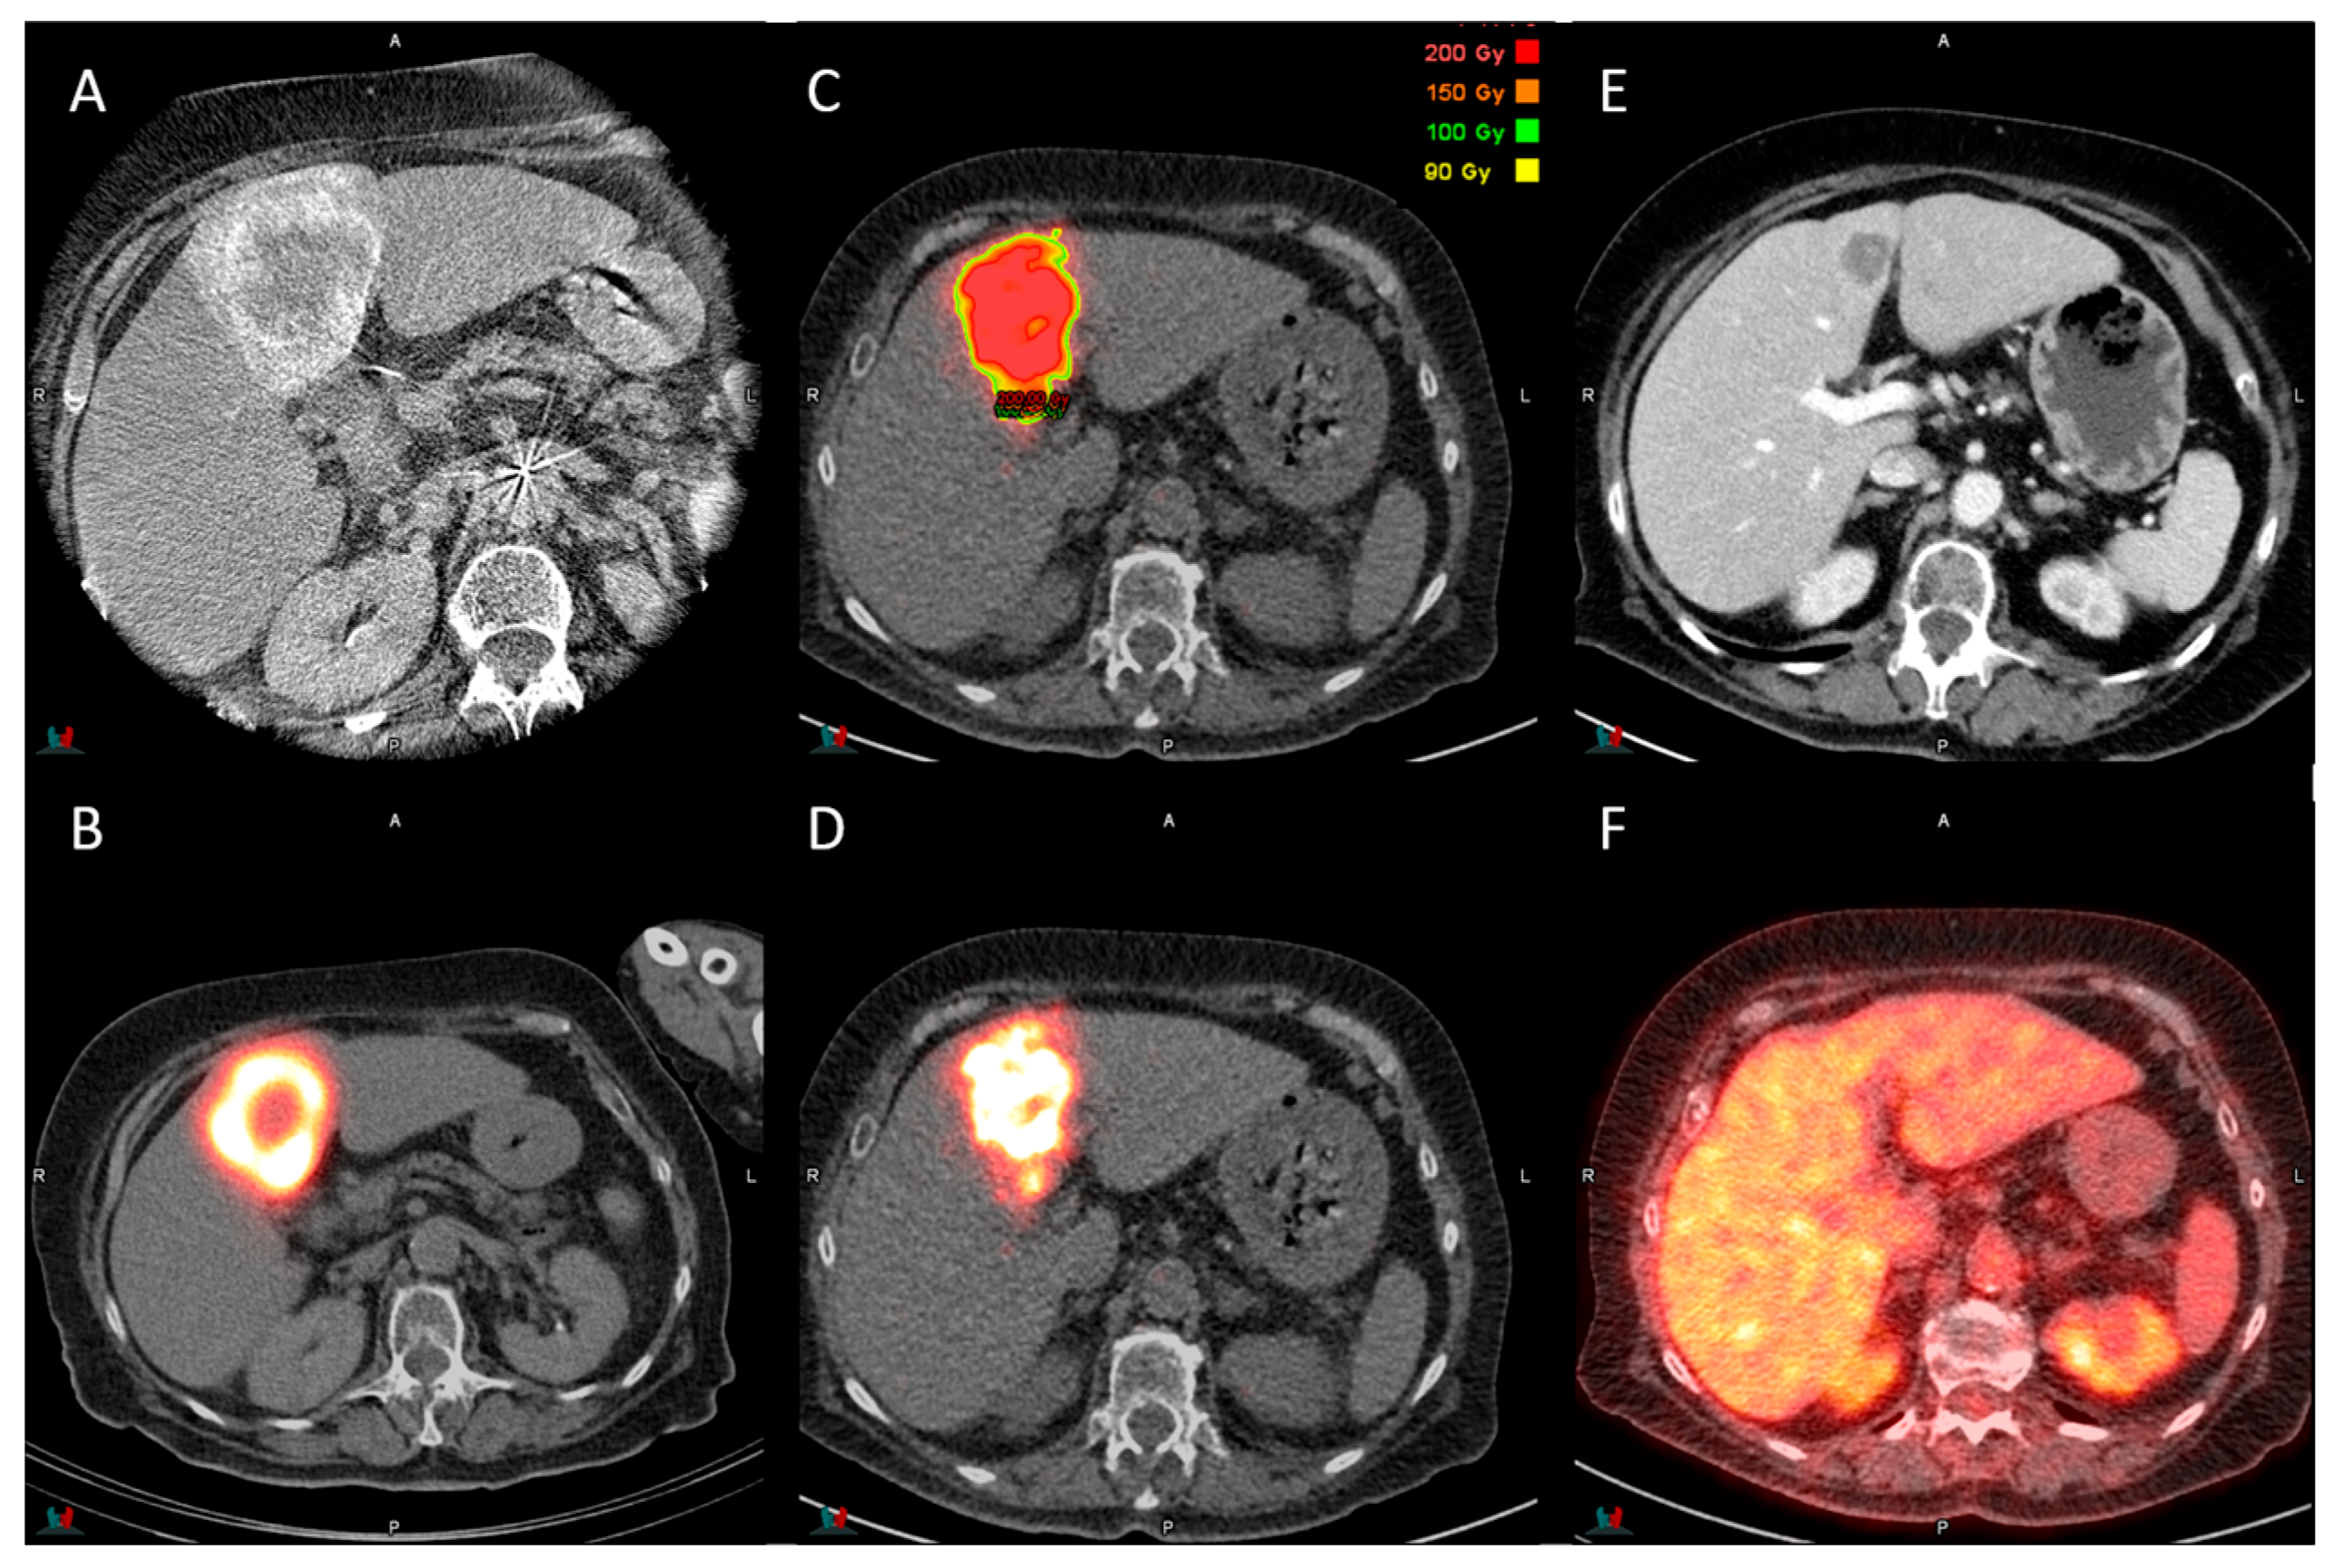

2.2. Procedure and Dosimetry Planning

2.3. Post-Treatment Dosimetry Analysis